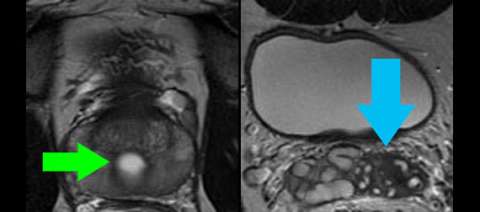

LEFT: Coronal high-resolution T2-weighted image shows a Muellerian duct remnant cyst in the superior prostate (green arrow) and atrophic seminal vesicles on one side only (blue arrow). A utricle cyst, which is much more common, would like lower in the prostate at the level of the verumontanum.